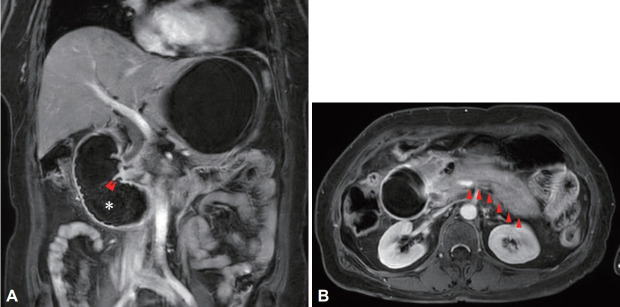

胃肠道牛黄通常是既往胃手术或胃肠道运动改变患者的并发症。胃肠道牛黄的并发症包括穿孔、腹膜炎、蛋白质丢失性肠病和急性阑尾炎。继发于十二指肠牛黄的急性胰腺炎是罕见的,很少有研究报道这种并发症。我们报告一例急性胰腺炎和随后的十二指肠梗阻引起的大十二指肠植物牛黄。

Gastrointestinal bezoars often occur as a complication of previous gastric surgery or in patients with altered gastrointestinal motility. Complications associated with gastrointestinal bezoars include perforation, peritonitis, protein-losing enteropathy, and acute appendicitis. Acute pancreatitis secondary to a duodenal bezoar is rare, and few studies have reported this complication. We report a case of acute pancreatitis and subsequent duodenal obstruction caused by a large duodenal phytobezoar.